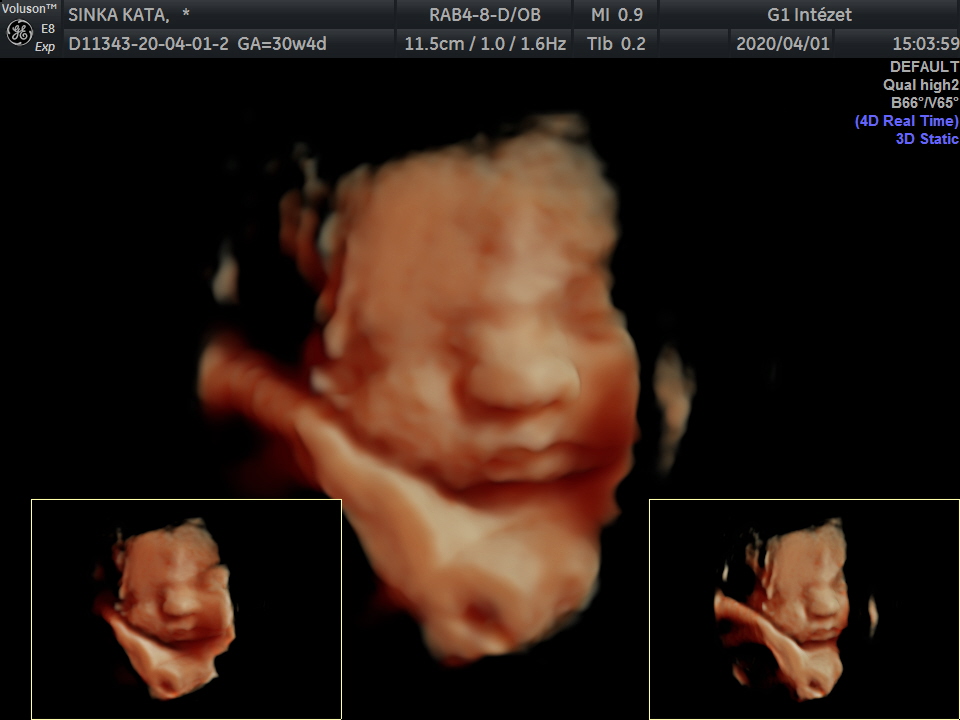

4D

Kérette magát egy kicsit, de azért készült jó kép